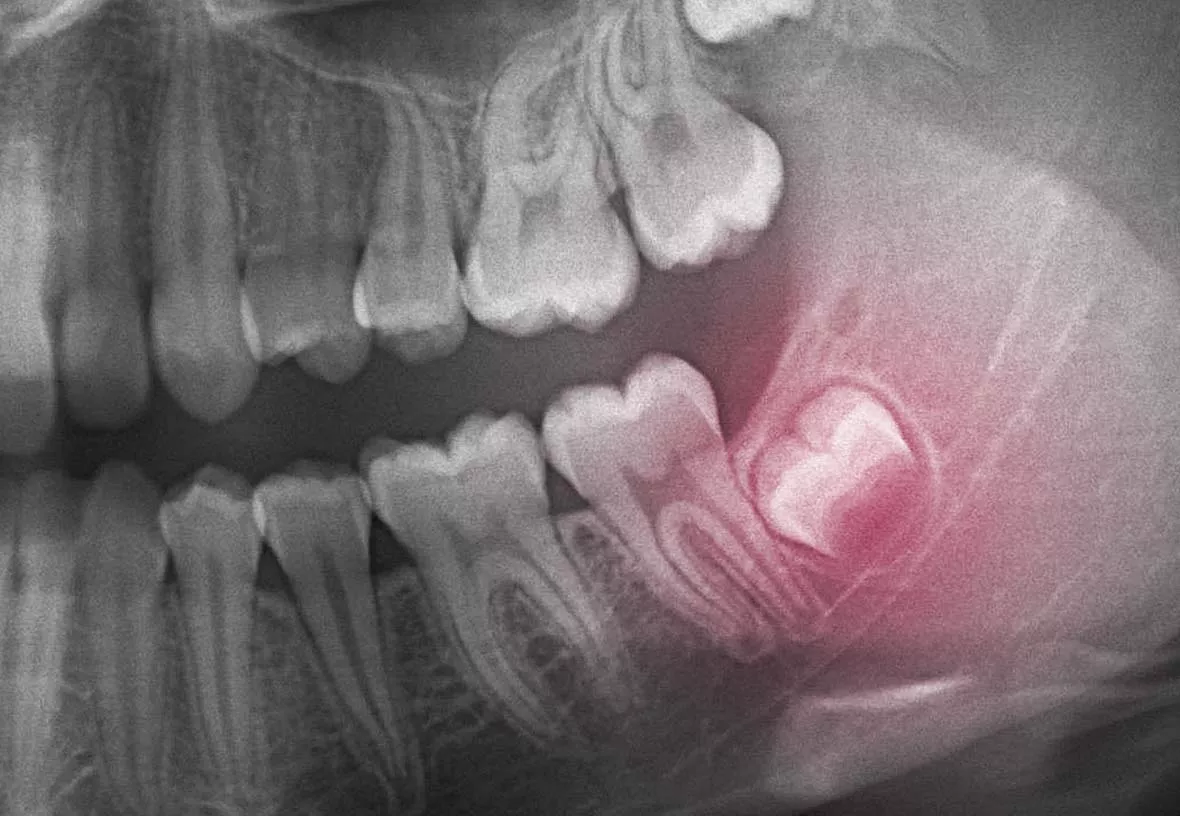

Your wisdom teeth are your last adult teeth. These large molars usually emerge behind your second set of molars at the back of your mouth. However, humans have evolved to have smaller jaws, and there is often not enough room in the jaw for the wisdom teeth to emerge correctly. When this happens, they can be crooked or grow under your other teeth and damage them. Your dentist will monitor the development of your wisdom teeth and recommend their extraction if they aren’t growing correctly.

The wisdom teeth are usually removed before they break through the gums. That means they need to be removed through surgery. Your dentist will make incisions near each tooth and then remove them. The treatment is done with a local anesthetic (freezing), and your dentist may also give you a mild sedative to help you stay relaxed during the procedure. After your wisdom teeth are removed, your dentist will usually close the incisions with sutures. You will usually be required to return to our office for a post-operative checkup to ensure you are healing as you should.